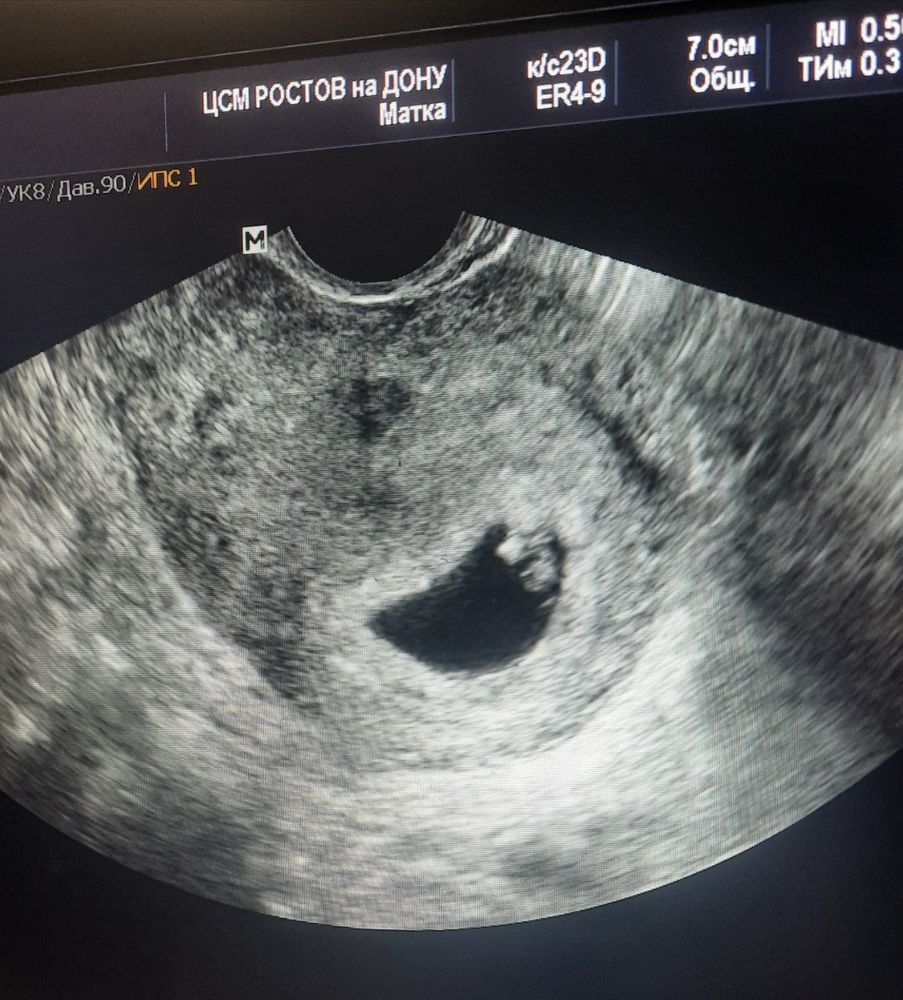

27дпп результаты узи